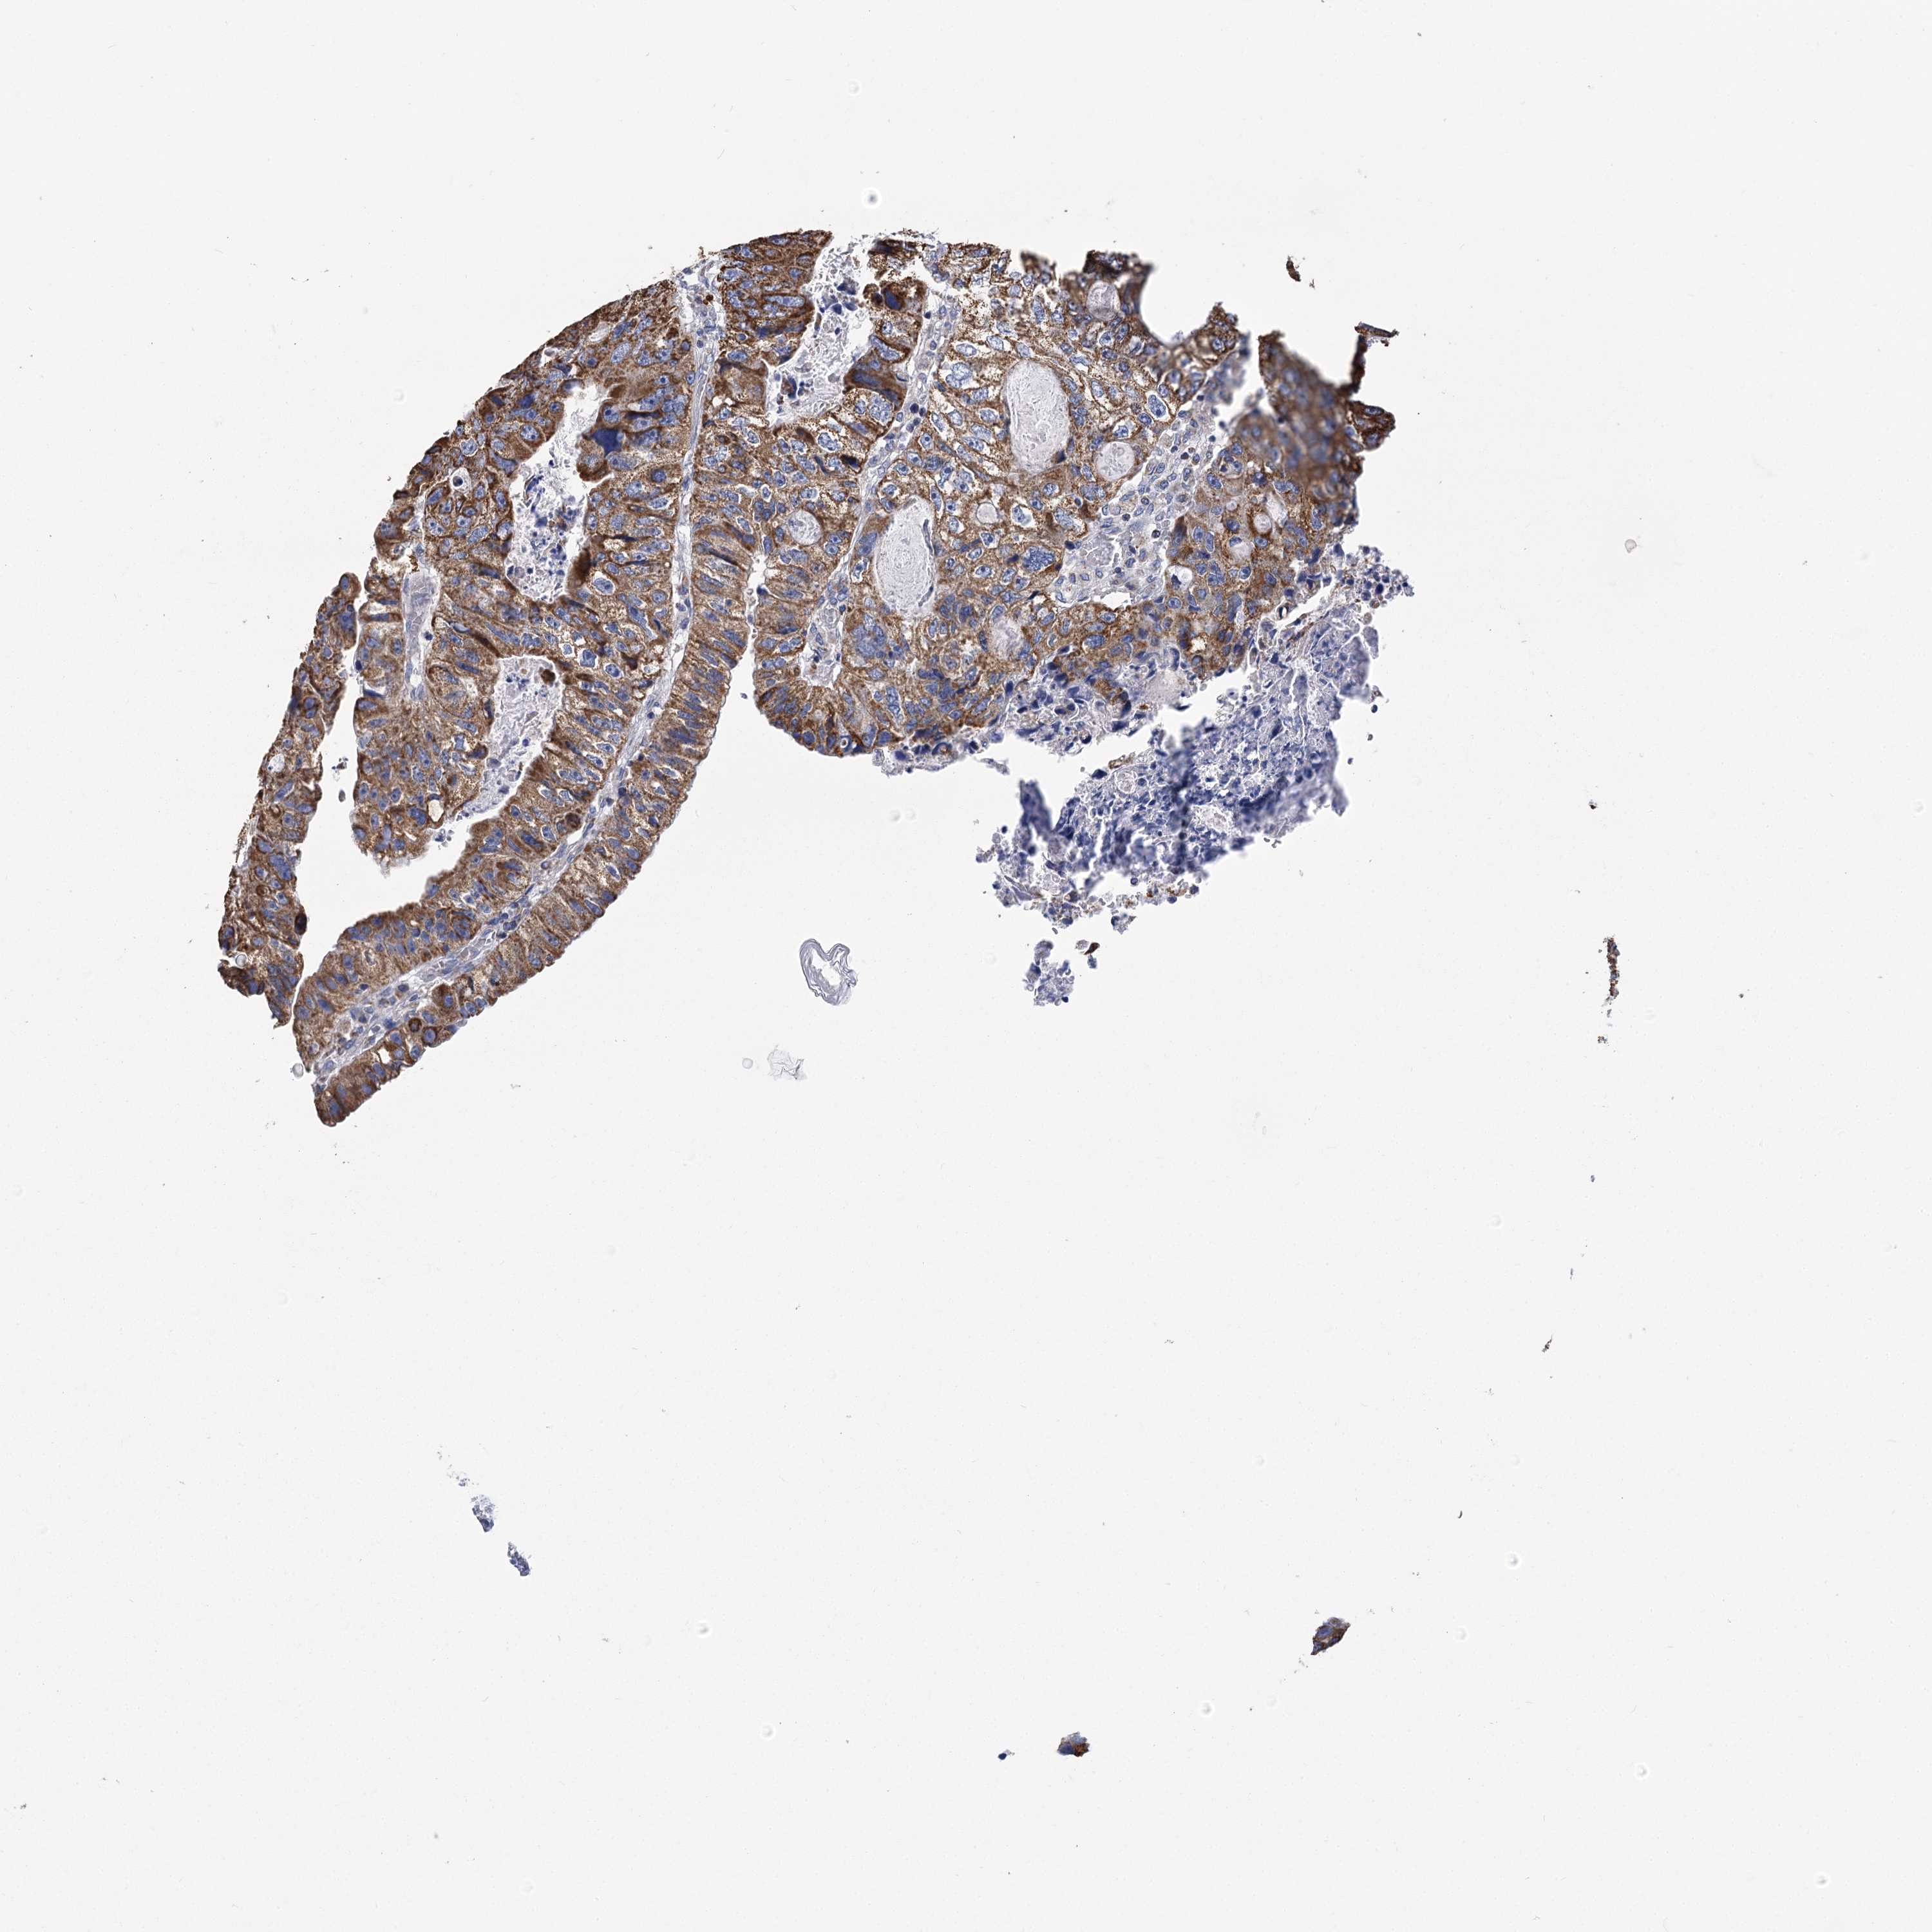

CANCER COLORECTAL CANCER Show tissue menu

Colorectal cancer

Human cancer

Colon adenocarcinoma